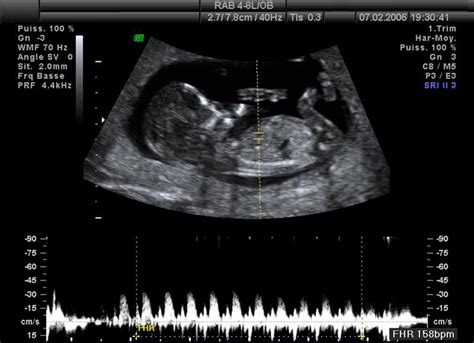

Genetické vyšetření plodu - I. trimestrální screening v 11. až 13. týdnu těhotenství